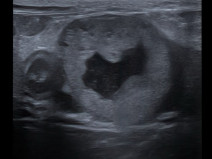

• Radiologie interventionnelle : se lancer et voir plus loin !

Le Groupe d'Étude en Chirurgie est heureux d’organiser sa 9è journée spécialisée sur le thème de la radiologie interventionnelle, le 29 janvier 2026. Cette journée annuelle de formation vise un public de vétérinaires ayant un fort intérêt pour la chirurgie des tissus et la chirurgie mini-invasive. Elle se tiendra au siège de l'AFVAC Paris 8è.

Cette année, nous avon...

Le 29 janvier 2026

Paris (75008)

Chirurgie

Oncologie

G.E.C.

2080